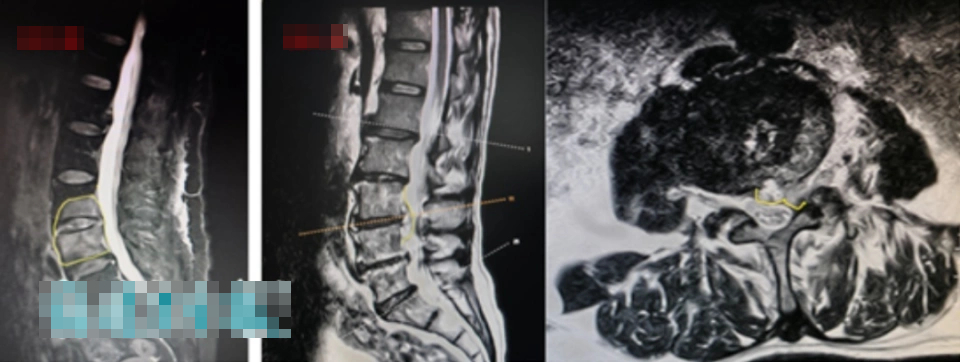

Sau khi tham khảo ý kiến chi tiết và khám sức khỏe, bác sĩ đã đưa ra chẩn đoán sơ bộ rằng cả hai người có thể mắc bệnh viêm cột sống liên quan đến bệnh Brug. "Các mẫu máu được lấy để xét nghiệm, và các kiểm tra liên quan như chụp cộng hưởng từ (MRI) cũng được thực hiện".

Vài ngày sau, kết quả xét nghiệm đã có - cả hai vợ chồng đều “dương tính với kháng thể brucellosis”; chụp cộng hưởng từ (MRI) cũng cho thấy có dấu hiệu viêm rõ ràng ở các khoảng gian đốt sống và các đốt sống liền kề của cột sống thắt lưng.

Trong đó, tình trạng của chồng bà Trương nghiêm trọng hơn: cột sống thắt lưng của ông không chỉ bị nhiễm trùng mủ mà tình trạng viêm nhiễm còn lan vào ống sống, khiến cột sống thắt lưng của ông trở nên vô cùng không ổn định. Ông có nguy cơ gặp phải những hậu quả nghiêm trọng như tê liệt và đau nhức ở chân, yếu cơ, thậm chí là liệt toàn thân và tiểu không tự chủ bất cứ lúc nào.